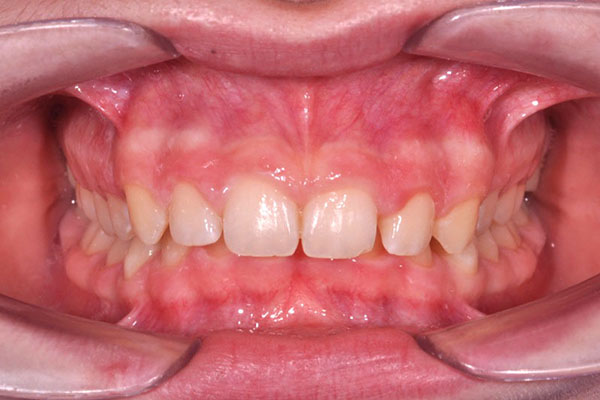

Overjet aumentato con incisivi superiori molto sporgenti (così detto aspetto del Brutto anatroccolo)

Il trattamento ortodontico nel bambino con “denti sporgenti” consente, ottimizzando il tempo di utilizzo delle apparecchiature, di ridurre il rischio di frattura traumatica dei denti anteriori, di migliorare l’estetica e di aumentare l’autostima del paziente (riducendo le conseguenze del bullismo di coetanei tipico di queste condizioni).